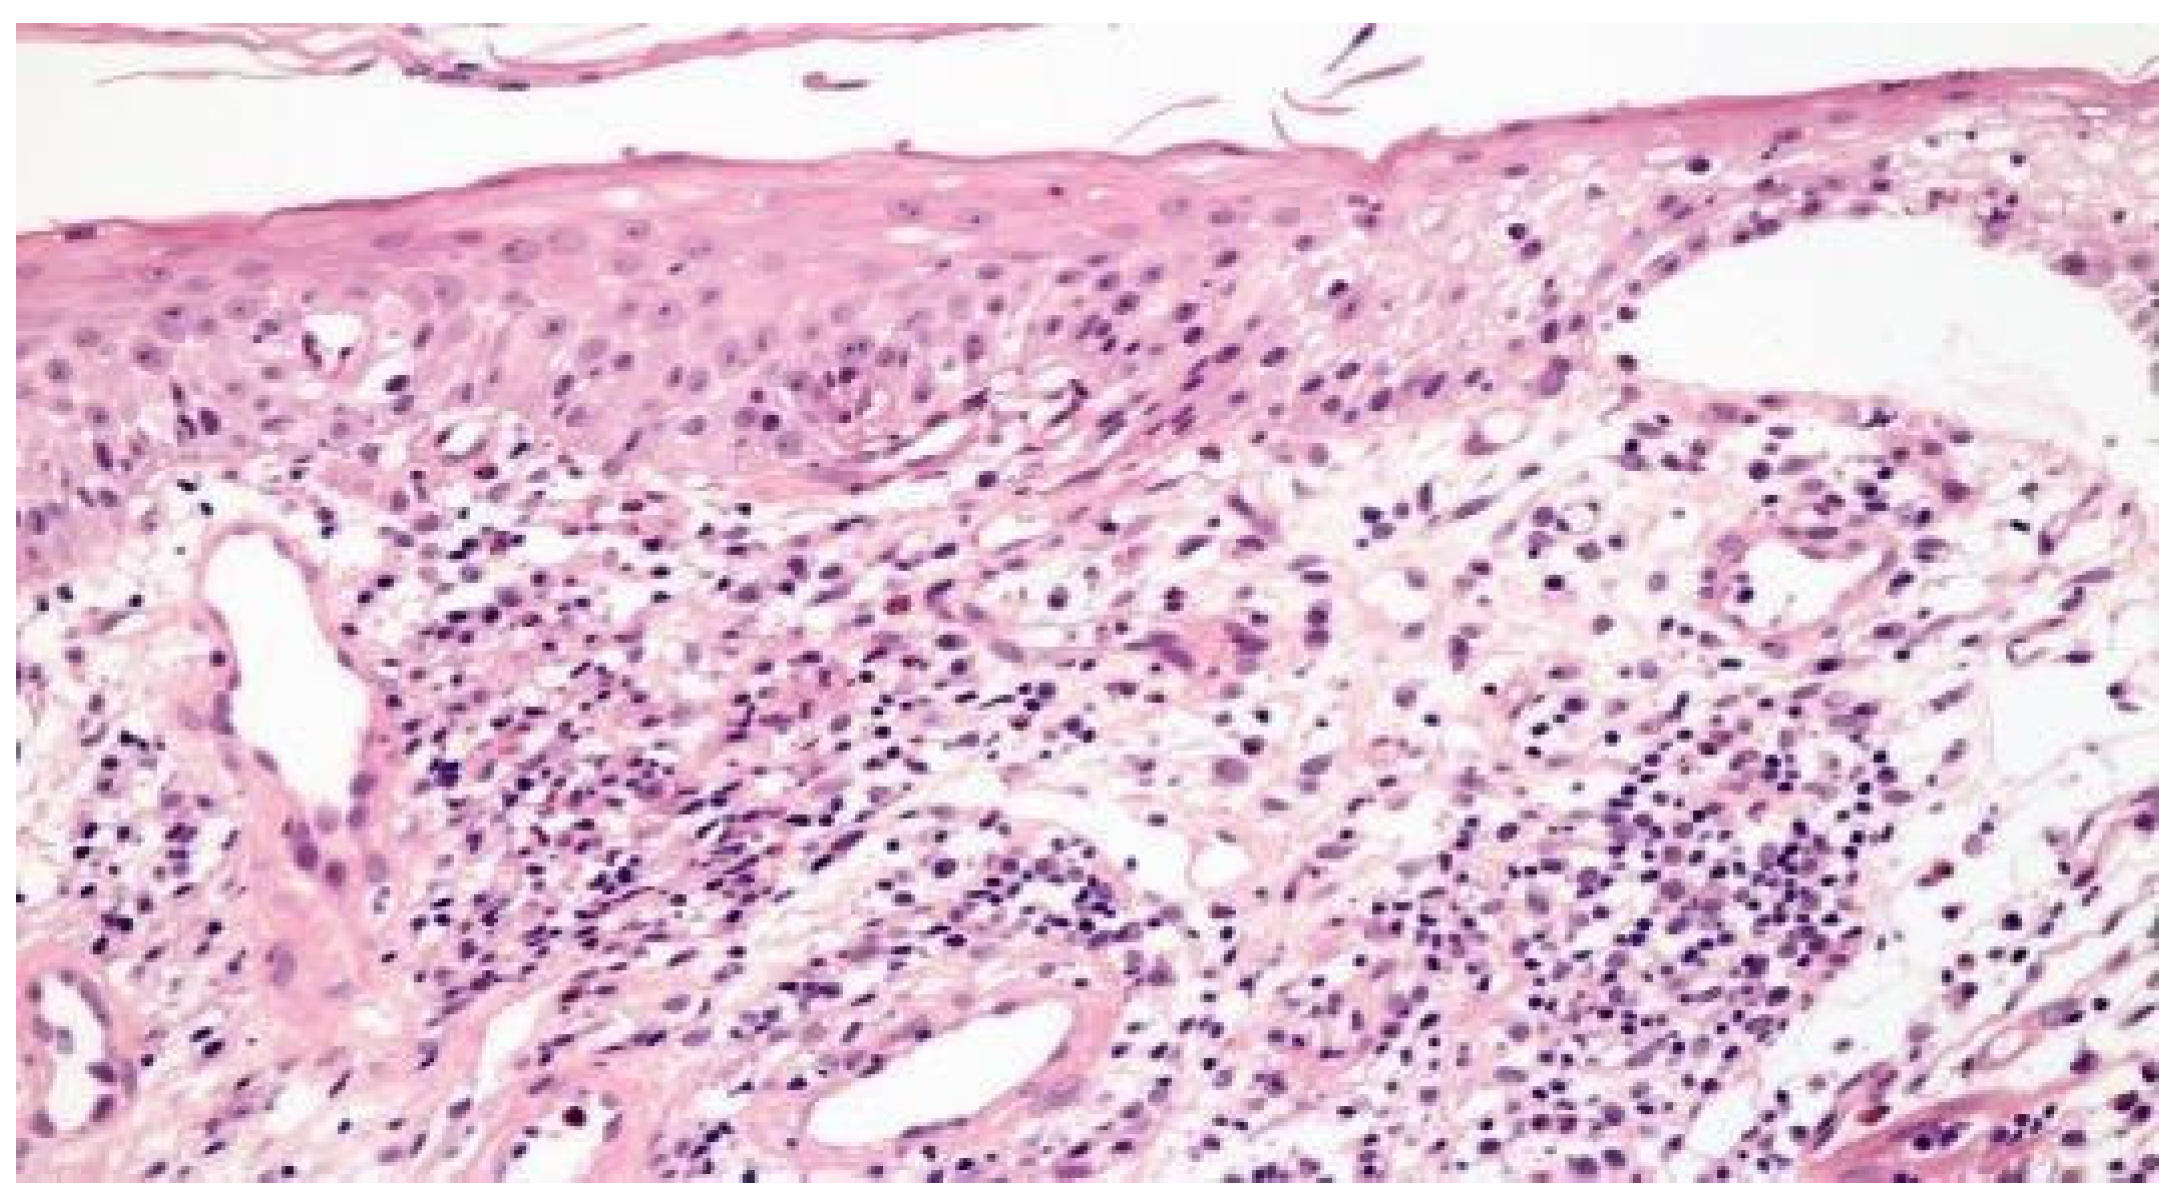

Figure 1 illustrates the histopathological findings in one patient with aphthous ulcer in distal esophagus.

Figure 1.

Focal esophagitis with spongiosis and subepithelial vesicle formation. Lamina propria with edema and mononuclear inflammatory infiltrate (H&E × 100).